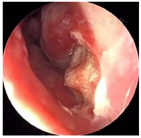

入院后完善术前常规检查,于次日在局麻下行切开引流术,阿替卡因肾上腺素行21-22前庭沟黏膜下局部浸润麻醉,麻醉显效后,自21-22前庭沟处切开黏膜及黏膜下层至囊腔约3 mm水平切口,见大量黄色分泌物溢出,取部分脓液做细菌培养,大量生理盐水冲洗至冲洗,留置橡皮引流条,术后常规予以抗生素控制感染。4 d后检查前庭沟切口处已愈合。经耳鼻咽喉科与口腔颌面外科会诊,决定行鼻内镜下左侧鼻底、下鼻道共同开窗肿物切除术。术中先用彭氏电刀电凝左侧鼻底及下鼻道隆起处黏膜(图5),剥离子自隆起处外侧刺破黏膜进入囊腔,见大量囊液流出,囊液呈浅褐色,略浑浊,吸净囊液后,向后扩大开窗口,保留后部黏膜瓣。剥离部分囊壁送病理检查,清除病变组织后,发现位于囊腔前下壁的不完全的骨间隔隆起(图6)。剥离子在囊肿的左侧上部探查见上颌窦内下骨质缺损,由此刺破软组织进入上颌窦,见有黏液涕流出,扩大上颌窦开窗口,动力系统清除病变组织,使囊肿腔与上颌窦形成一个腔(图7),修剪后部蒂瓣,使之正好贴敷于囊腔后壁(图8),反复生理盐水冲洗术腔,检查无残留,膨胀海绵填塞。手术过程见视频。手术顺利,术后继续行抗生素控制感染,48 h抽出鼻腔膨胀海绵,检查见鼻底及上颌窦开窗口开放良好,腔内有少许血性分泌物,黏膜略水肿。术后病理镜下见被覆鳞状上皮,间质内见急慢性细胞浸润(图9)。术后4 d患者康复出院。

本例患者囊肿范围较大,囊腔内有不完全骨隔形成,分析可能为两个上颌骨囊肿在扩展中互相融合而形成,影像学的变化和手术中的所见证实了这一点,囊肿同时累及了左侧鼻底及下鼻道,将左侧上颌窦底抬升,上颌窦内下的部分骨质吸收破坏。